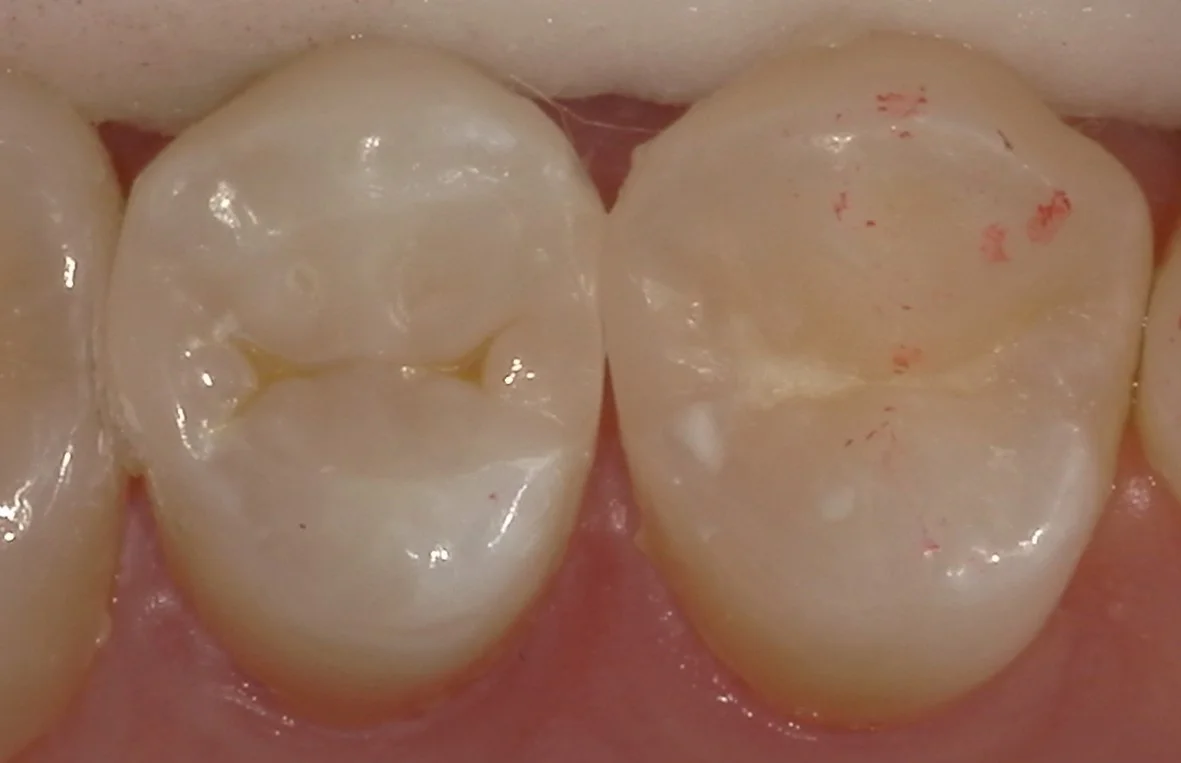

そして虫歯を取りきったのがこちらです。

ごっそりと歯が亡くなったのが分かるかと思いますが・・・

実は歯の表面のエナメル質の部分だけが残っている状態(遊離エナメルといいます)になります。

こういう状態の時にダイレクトボンディングでの治療という選択肢が無ければ、元気な神経を抜いて、被せ物を入れるという手法を取るしかなくなってしまいます。

あくまでも先生の考え方に左右されるのですが、なるべく神経を抜きたくないのであれば、こういった手法を行うことが出来る先生を選んでおいた方が良いこともあります。

(注:必ずしも神経を残すのが最善にはならないことも多々あります。)